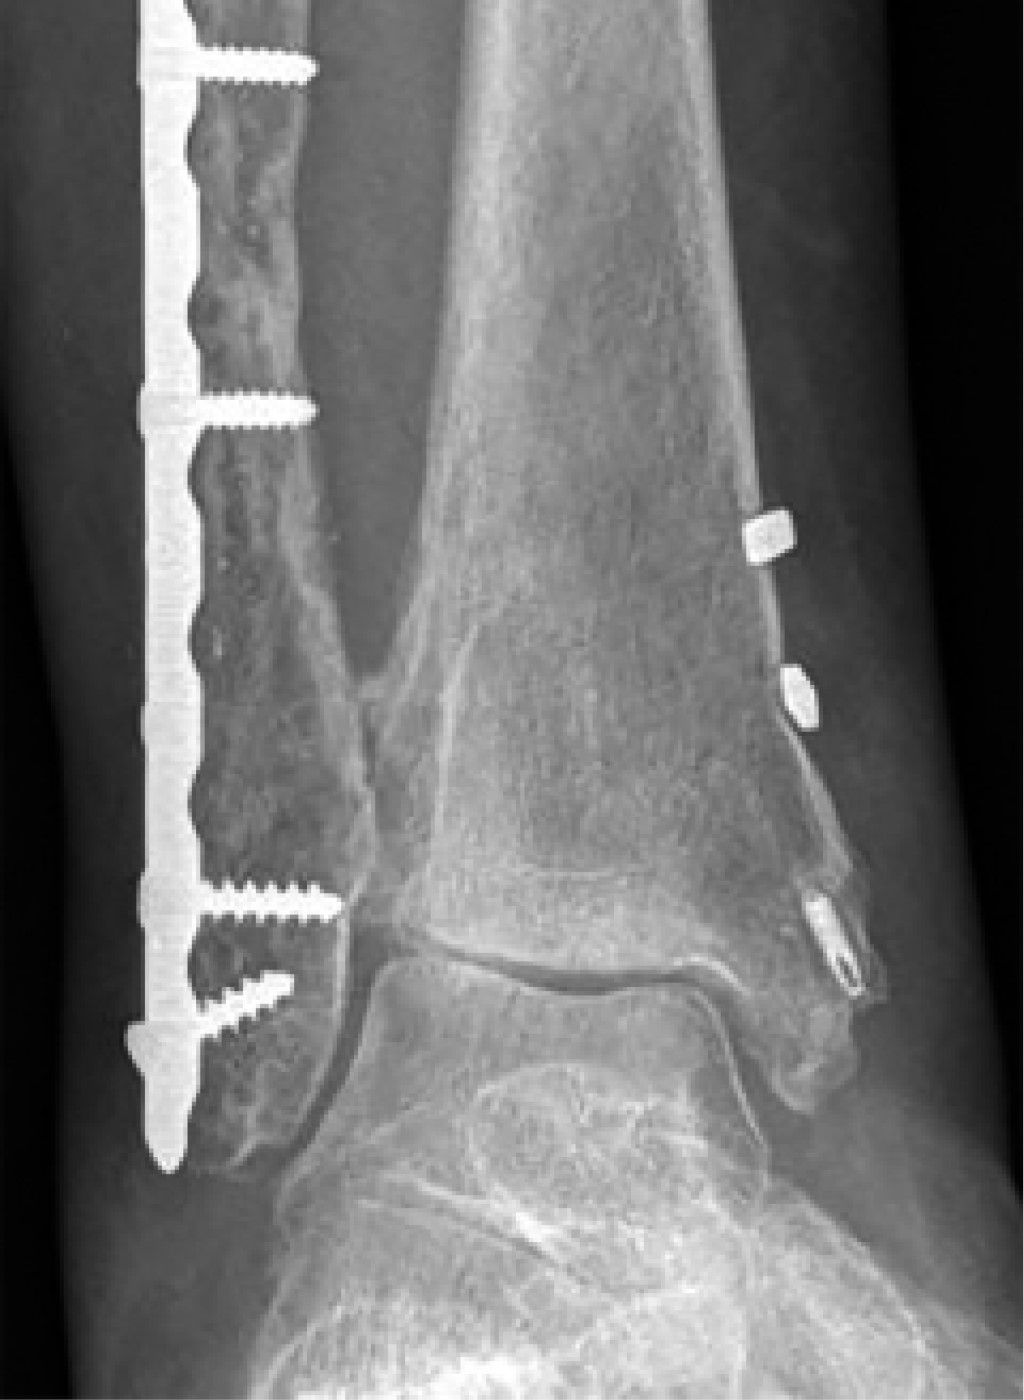

The first case is of a 27-year-old male, referred to our clinic seven months after internal fixation of an ankle fracture. A dorsiflexion deficit caused an abnormal gait due to a hard and sudden block at -30o in the right ankle (Figure 1). Plantar flexion was normal. The patient AOFAS Score was 78 points.

The AP ankle radiograph (Figure 2) showed an apparent congruent joint with a symmetrical clear space between the tibial articular surface and the talar dome, without internal augment. On a second look, an irregularity on the lateral facet of the medial malleolus could be noticed, as well as the incorrect vertical alignment between the tibia and the talus (Figure 2, zoom with circles).